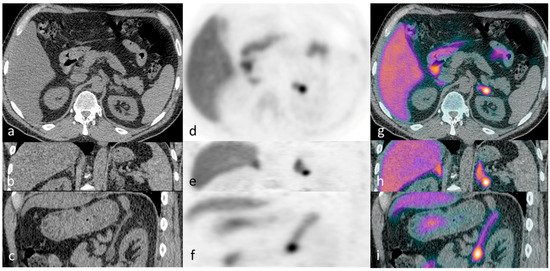

Figure 1. Illustrative case 1: A 65-year-old man with a ten-year history of hypertension and hypokalaemia, requiring multiple agents for blood pressure control (including eplerenone) and oral potassium supplementation, was diagnosed with primary aldosteronism. CT demonstrated a lipid-poor 12 mm left adrenal nodule - displayed in axial, coronal and sagittal planes (ac). 11C-metomidate PET-CT [(df) (PET) and (gi) (PET-CT)] confirmed increased tracer uptake in the left adrenal nodule. The patient underwent laparoscopic left adrenalectomy, with subsequent histology confirming a classical Conn’s adenoma. Post-operatively, he had complete resolution of his hyperaldosteronism with excellent blood pressure control on progressive down-titrating medications (currently two agents with further weaning planned), and with no requirement for supplemental potassium at four-month follow-up. For comparison, axial PET/PET-CT images are shown as reconstructed via “time-of-flight” (TOF) iterative algorithms: without (j,k) and with resolution modeling (SharpIR) (l,m).